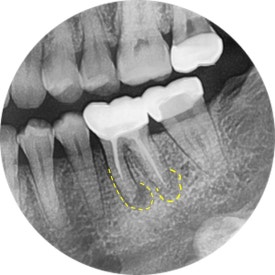

파노라마 엑스레이로 전체 치아들을 조망하겠습니다.

역시나...

왼쪽 아래에 신경치료 받은 치아가 심상치 않아보이네요.

파노라마를 확대해보니,

앞선 프랑스 유학생의 사례와 마찬가지로

이전에 신경치료 받은 치아에서 염증이 시작되고 있었습니다.

곧이어 치근단엑스레이를 찍어보았지요.

어금니는 뿌리가 여러개기 때문에, 경우에 따라 각도를 달리하여

2장 이상 촬영하기도 한답니다.

통상 아래 어금니에는 신경이 4개 (적으면 3개, 많으면 5개) 있게 마련이죠.

그런데 조금 이상합니다.

4개 중에 2개가 뿌리 전체 길이에 못미치게 치료가 되어 있습니다.